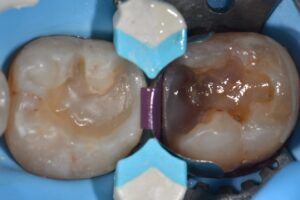

// Wide 2-stage large interdental space closure with DME using the #Garrison Strata-G matrix system